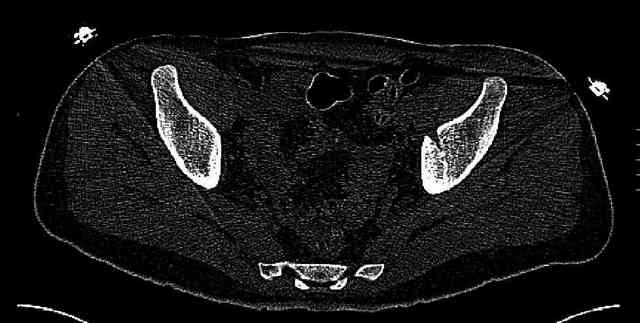

While not claiming to have the best 3D brain around, it appears to me from the limited images available, that the caudal segment is stable from the symphysis to the SI joint on the fracture side. I would love to see the rest of the transverse CT images to see where the fracture line actually exits posteriorly on both the inner and outer tables of the ilium. In my hands,

Some more images. Does it help to guess which part of the acetabulum is displaced?

Normal appearing SI joints and a healed posterior column limb... my bet's on caudal segment displacement.